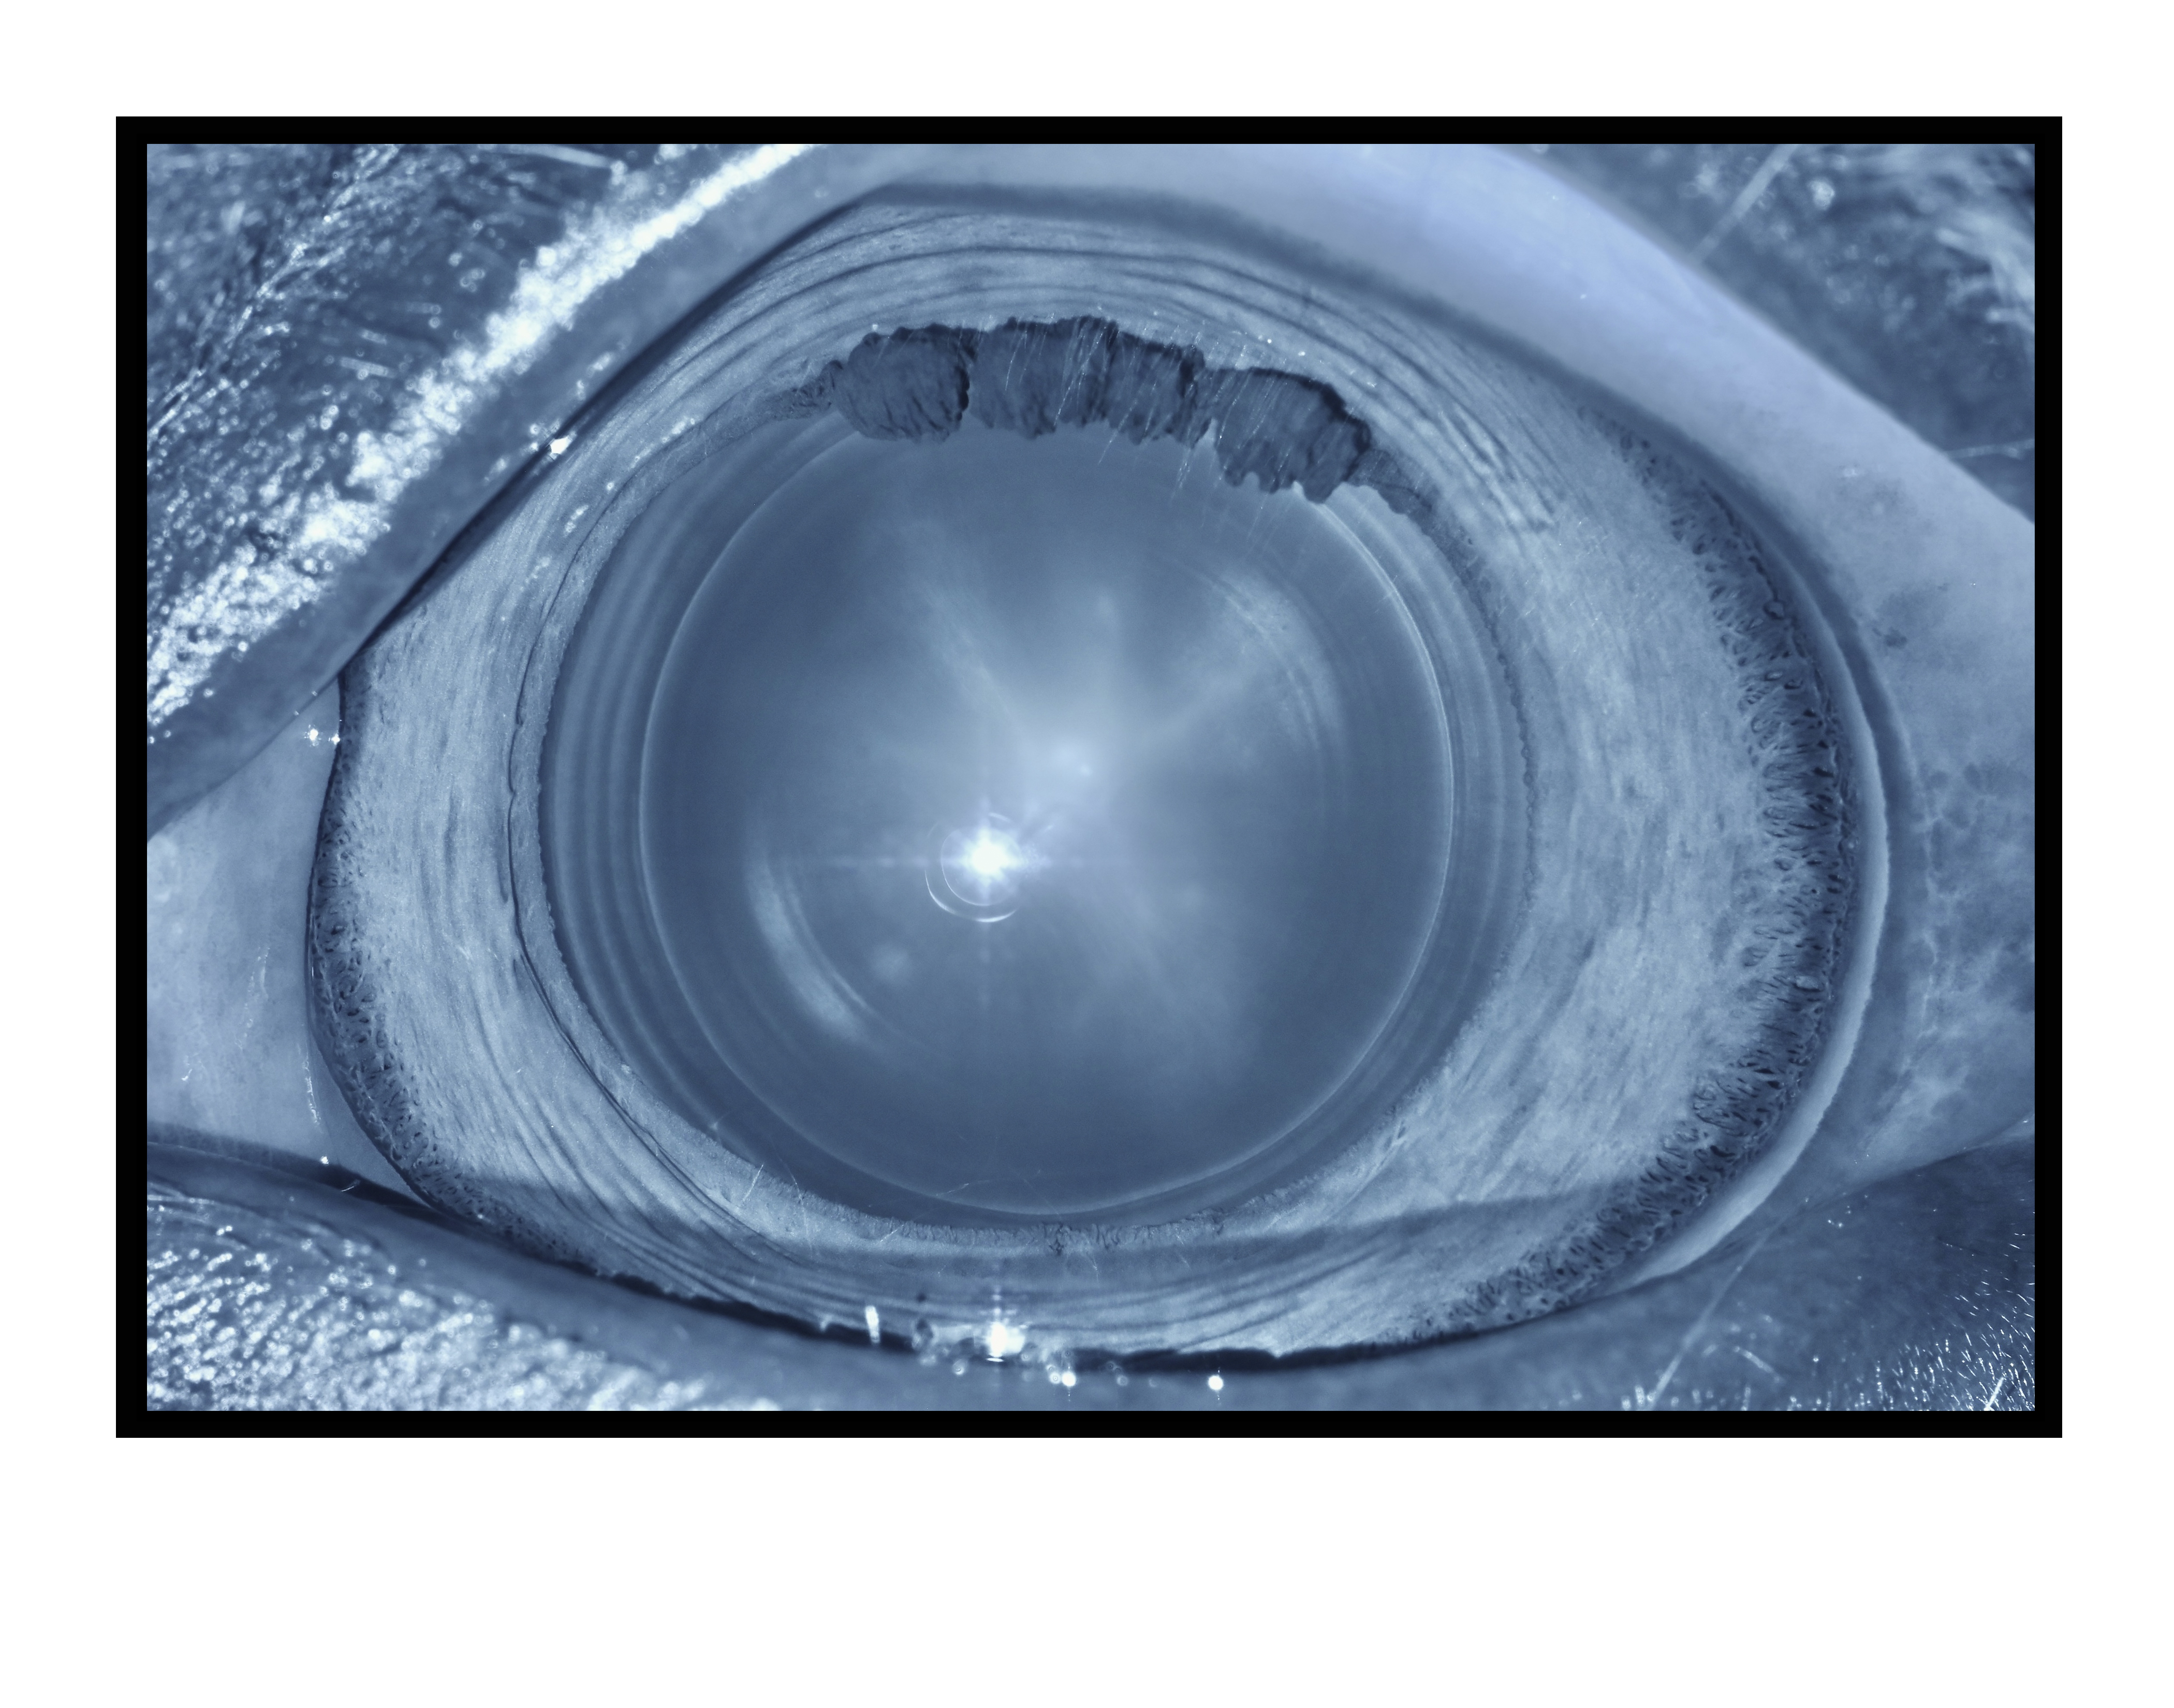

Zones of Discontinuity Equine Lens Presented by Richard McMullen, Jr. This photograph received Honorable Mention in the category "Monochromatic Photography" and was displayed in the 2024 OPS Exhibit. Filed Under Cataract OPS Photo